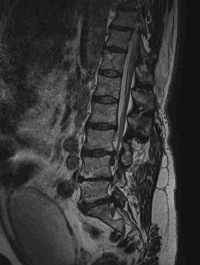

Sténose lombaire

Spondylolisthesis lombaire

Discopathies